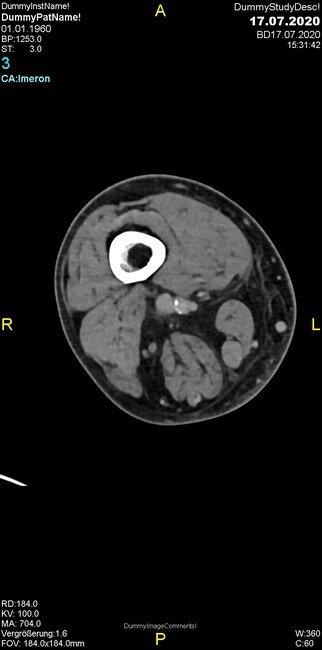

Um welche Modalitäten handelt es sich?

- Röntgen p.a. und lateral, CT coronar Knochenfenster, CT axial Weichgewebsfenster

Was fällt in der CT im Knochenfenster auf?

- Mediale Gelenkspaltverschmälerung

- Dezente Erosion der fibulären Kortikalis

- Frakturspalt der lateralen Tibiametaphyse

- Weichgewebskalzifikationen lateral angrenzend an den Gelenkspalt

- Osteolyse der Tibiametaphyse unter Beteiligung der Kortikalis